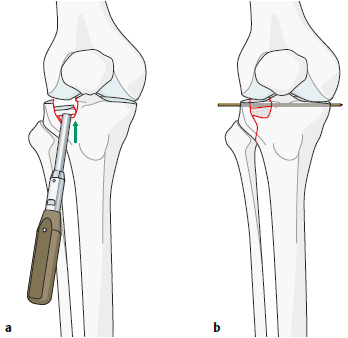

图6.8.1-15a-b

关节面塌陷必须使用顶棒小心地抬高,顶棒可以经由骨折线或者开一个小皮质窗插入

关节内骨折的复位通常需要切开关节囊后,直视关节时进行操作。对于外侧胫骨平台骨折,可以向外翻转骨折块及其软组织附着,以直视关节面的压缩。塌陷的区域和骨块可以从下方使用顶棒仔细地抬高;股骨髁可以作为复位的参考模板(图6.8.1‑15),此时应同时留意髁间窝区域,特别注意一下前、后交叉韧带的情况。